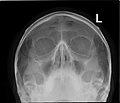

Paranasal Sinuses lat.jpg

Lateral projection of the paranasal sinuses